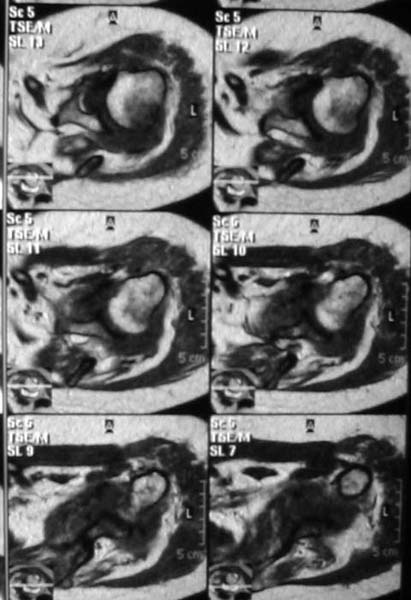

Уважаемые коллеги!Женщина, 60 лет. 3 недели назад упала с упором на отведенную левую руку. Почувствовала боль в левом плечевом суставе. За помощью не обращалась. 2 недели "мази и припарки". Затем - рентгенограмма (r1 и r2), жалобы на боли,ограничение движений...

Активное отведение 80 гр., при пальпации - головка плечевой кости безболезненно вправляется и тут же самостоятельно вывихивается. Наложена косыночная иммобилизация, рентгенография (r3) и МРТ.В нашем диагностическом центре МРТ исследование плечевого сустава выполнено впервые, опыта у нас маловато :(.Вопросы: уточнение диагноза? какие исследования провести? тактика лечения?

МРТ1МРТ2МРТ3МРТ4

Из того, что видно на недостаточно качественно отсканированных МРТ - нижний подвывих плеча и синовиит. Непонятный очаг по заднему контуру головки плеча (то ли артефакт, то ли косой срез, проходящий между головкой и большим бугорком). Сухожилия вращательной манжетки выглядят целыми. Неправильная форма нижней части labrum glenoidale - разрыв ?

МРТ должен показать разрыв манжетки, но признаться я не большой эксперт по чтению МРТ сканов, хотя затемнение, отек мягких тканей по задней поверхности плеча видны Обычные рентгенограммы демонстрируют остеолизис в области большого бугорка.

1. На рентгене - нижний подвывих плеча и очаг остеолиза суставного бугорка с четкими контурами (вдавленный перелом на фоне остеопороза ? доброкачественная опухоль? аваскулярный некроз ? (хотя ни разу не слышал об аваскулярном некрозе плеча..)

2.выраженный выпот в полости сустава

Судя по снимкам, речь идTт о типичном случае Hill-Sachs Lesion. По этому поводу я позволю себе некоторый экскурс:

97 % всех вывихов плеча происходит по механизму комбинации отведения, разгибания и наружной ротации (А. Гринспан). В момент вывиха головка плеча ударяет о нижний край гленоида, что ведет к вдавленному или компрессионному перелому одной или обеих структур. Чаще всего, однако, повреждение возникает в задней латеральной области головки плечевой кости на переходе от головки к шейке. Этот диагноз можно выставить на основании рентгеновского снимка в переднезадней проекции с внутренней ротацией плеча. Несколько реже видно повреждение гленоида о передненижний перелом края. То, что мы называем Bankart Lesion. Это повреждение видно на ре. снимке в п.з. проекции при нейтральной позиции плеча. Разумеется хрящевые и мягкотканные повреждения (в смысле Банкарт) мы увидим лучше всего на ЯМР.

Учитывая описанную клинику, речь идTт о комбинации патологии. К сожалению, учитывая качество снимков NMR, я не могу провести достаточно точную верификацию состояния нижнего края гленоида, что впрочем, не меняет рекомендации. Для определения состояния РМ и дополнить исследование УЗИ мягких тканей плеча. В опытных руках достаточно информативное и дешевое исследование.